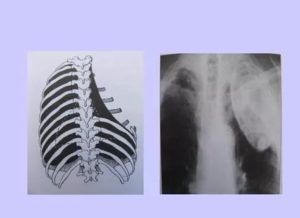

Еще одна разновидность операции на легких – торакопластика. Применяется в тех случаях, когда противопоказано проведение резекции органа. Ее суть – удаление ребер со стороны пораженного легкого.

После проведения торакопластики рекомендовано ношение тугой повязки на протяжении нескольких месяцев. В течение этого времени пациент испытывает сильную боль, недостаток кислорода, одышку и учащенное сердцебиение.

Торакопластика – это малоинвазивный метод оперативного вмешательства, который зачастую применяется в тех случаях, когда необходимо провести санацию органа без надобности его резекции.